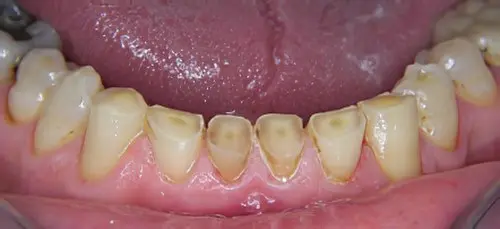

- DENTS et PROTHESES (couronnes, appareils…) : usures, fêlures, fractures, mobilités, sensibilités….